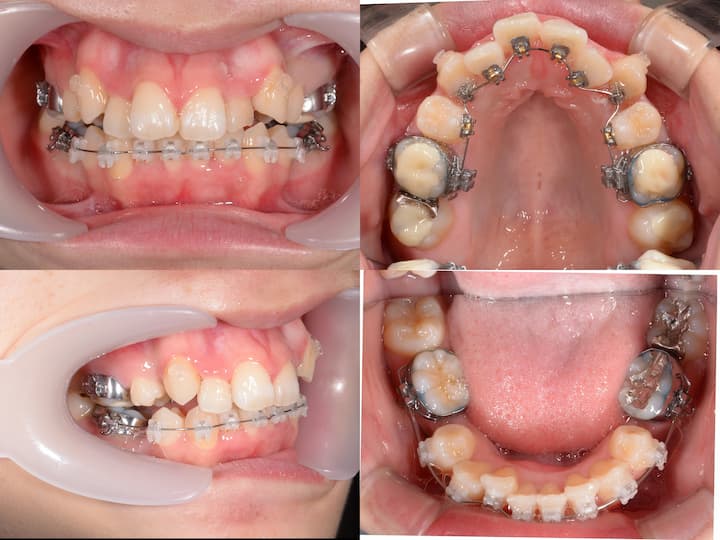

症例概要

本症例は、叢生および口唇部の突出感を主訴とする患者様に対し、ハーフリンガル矯正装置(上顎舌側・下顎唇側)を使用して治療を行いました。

下顎骨の後方位を伴うハイアングル症例であったため、上顎大臼歯の圧下を治療計画に組み込み、下顎骨のアンチクロックワイズローテーション(反時計回り回転)を誘導することで、口唇部の突出感改善と良好な咬合関係の確立を目指しました。

初診時年齢:27歳2ヶ月

主訴:歯列不正および口唇部の突出感

初診時の口腔内所見および頭部X線規格写真分析より、以下の所見が認められました。

・上下顎前歯部の叢生

・口唇部の突出感

・AngleⅠ級臼歯関係(良好な臼歯関係)

・下顎骨の後方位(ハイアングル症例)

・下顎下縁平面角の増大

・上下左右第一小臼歯の抜歯による叢生の改善

・上顎大臼歯の圧下による下顎骨のアンチクロックワイズローテーション誘導

・AngleⅠ級臼歯関係の維持

上顎大臼歯の圧下により下顎骨を反時計回りに回転させることで、オトガイ部の前方移動と下顔面高の減少を図り、口唇部の突出感を改善する計画としました。

ハーフリンガル矯正装置を採用し、上顎は舌側矯正装置(リンガルブラケット)、下顎は唇側矯正装置(ラビアルブラケット)を使用しました。

・i-station(歯科矯正用アンカースクリュー)の植立:正中口蓋縫合部に植立し、上顎大臼歯の固定源として使用

・上顎大臼歯の圧下:i-stationからの圧下力により、上顎大臼歯を垂直的に圧下

・上顎大臼歯の固定:抜歯スペース閉鎖時の近心移動を防止し、AngleⅠ級臼歯関係を維持

・フルサイズワイヤーの使用:.018×.025インチTMA(チタンモリブデン合金)ワイヤーを使用し、臼歯部のみが選択的に圧下するように設計

・パラタルバーの装着:上顎大臼歯の幅径を維持し、歯列弓形態の安定を確保

・前歯部の垂直的位置の維持:大臼歯圧下時に前歯部が挺出しないよう、ワイヤーで適切にコントロール

総治療期間:1年5ヶ月

通院頻度:月1回